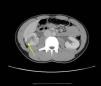

Presentamos el caso de un paciente varón adolescente de 13 años de edad que fue trasladado a nuestro servicio de urgencias después de una caída sobre la espalda desde 3 m de altura cuando trataba de realizar un salto mientras practicaba parkour. Presentaba dolor abdominal periumbilical irradiado a la fosa renal derecha, acompañado de hematuria macroscópica. Se constató defensa abdominal con percusión renal derecha positiva. La cifra de hemoglobina era de 14,2 g/dl, de creatinina de 0,75mg/dl y de urea de 18mg/dl, con estudio de coagulación normal. Las cifras de presión arterial eran de 104/67mmHg. El paciente no tenía fracturas costales. La ecografía abdominal reveló un área hipoecoica triangular de base periférica en el riñón derecho, asociada con una cantidad mínima de fluido perirrenal; el riñón izquierdo era normal. Las imágenes de la tomografía computarizada (fig. 1) mostraron una laceración renal derecha en su región inferior que, de acuerdo a la Organ Injury Scale of the American Association for the Surgery of Trauma (AAST), equivalía a un grado iv (laceración parenquimatosa que se extiende a través de la corteza renal, médula, y sistema colector)3. El paciente fue remitido a nuestra Unidad de Cuidados Intensivos Pediátricos. Fue valorado por el Servicio de Cirugía Pediátrica y se decidió tratamiento conservador. Permaneció en reposo con sondaje vesical y antibioterapia por vía intravenosa (amoxicilina-ácido clavulánico). A las 48 h del ingreso, la ecografía abdominal confirmó la desaparición de la colección perirrenal derecha y solo mostró un aumento de la ecogenicidad del polo inferior renal. Presentó hematuria macroscópica durante una semana. A los 8 días del ingreso el paciente fue dado de alta, con diuresis normal y sin hematuria.